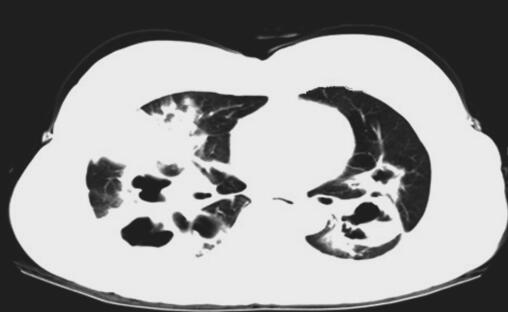

患者入院后考虑肺囊肿继发感染,给予抗感染治疗,完善相关检查,血常规:WBC 11.19×109/L,N% 68.90%;肺肿瘤标志物:CEA 2.46ng/ml,CYFRA 4.34ng/ml,NSE 9.38ng/ml;胸部CT示双肺气液囊肿并感染可能(图1);绒毛膜促性腺激素(β)HCG-BETA 5.48mIU/ml;电子支气管镜镜检未见异常;电子支气管镜肺活检病理示:子宫胎盘部位滋养细胞肿瘤肺转移。

图1 肺CT示双肺气液囊肿并感染可能

此例患者胸部CT提示双侧肺野多发液气囊性改变,考虑与滋养细胞在肺内破坏血管壁进入肺泡,使周围组织发生炎性浸润、出血、水肿,各肺泡病变融合成团,中心坏死,形成囊肿样改变,同时滋养细胞进入呼吸性细支气管为中心的细支气管周围组织发生炎性浸润,使呼吸性细支气管狭窄、闭塞,当囊肿内黏液潴留过多,或继发化脓性感染时,囊腔易与呼吸性细支气管穿透,形成单向性活瓣样通气,从而导致囊腔内压力不断升高,形成张力性液气囊肿改变。